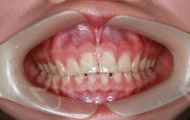

最后给大家展示一下口内的效果吧,如果我不说你能看到我戴了牙套吗?发音也还好,跟没戴牙套之前没有什么区别呢~

接下来去拍片的时候,还有护士姐姐给穿放射服,服务要不要这么周到~~来前我做好拔牙准备了,但医生给我制定的方案不需拔牙,因为收紧牙缝就好,还是小高兴了一会儿~拍了口内照、正面、侧面、45度的照片,OMG!设备简直不要太先进,医生讲解的很耐心,真的内心有点迫不及待了!!!